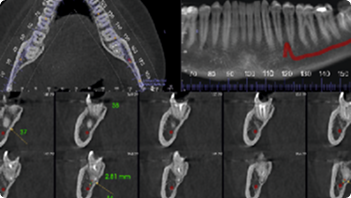

Pre-Implant Assessment

Impacted Tooth